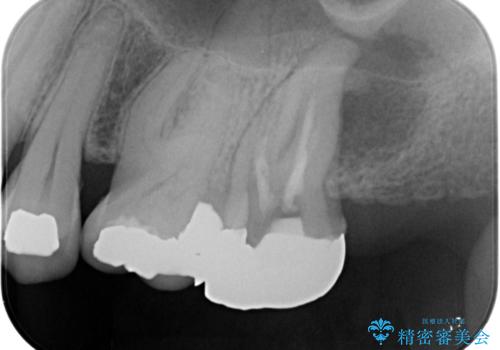

痛みはないとの事でしたがレントゲンを撮影したところ根の先に病巣がある事がわかりました。

被せ物、古い材料を徹底的に除去し、ラバーダム防湿にて無菌的処置を行い、セラミックの被せ物で治療を行いました。

治療が終了してからも定期的にレントゲンをとり経過観察を行いました。

病巣は現在縮小しておりまた白い被せ物が入り患者様に満足してもらえました。